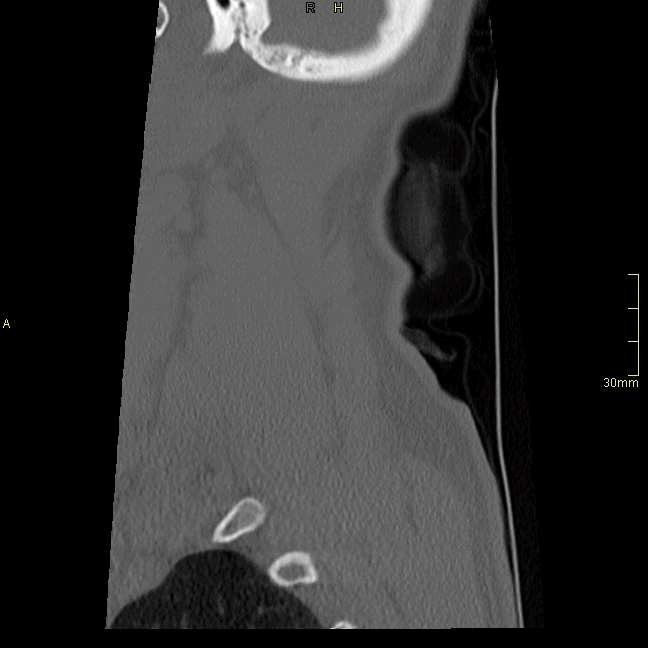

CT Cervical Spine Non Contrast- Bone window (Sagittal)

CT Cervical Spine Non Contrast- Soft Tissue window (sagittal)